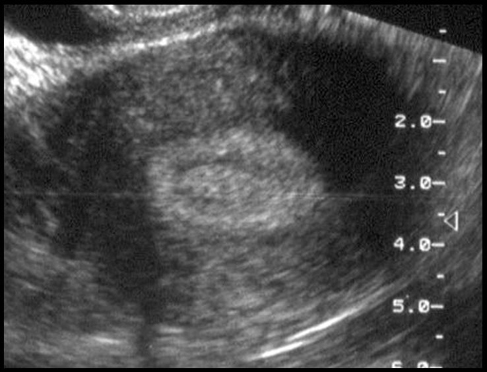

Polype muqueux